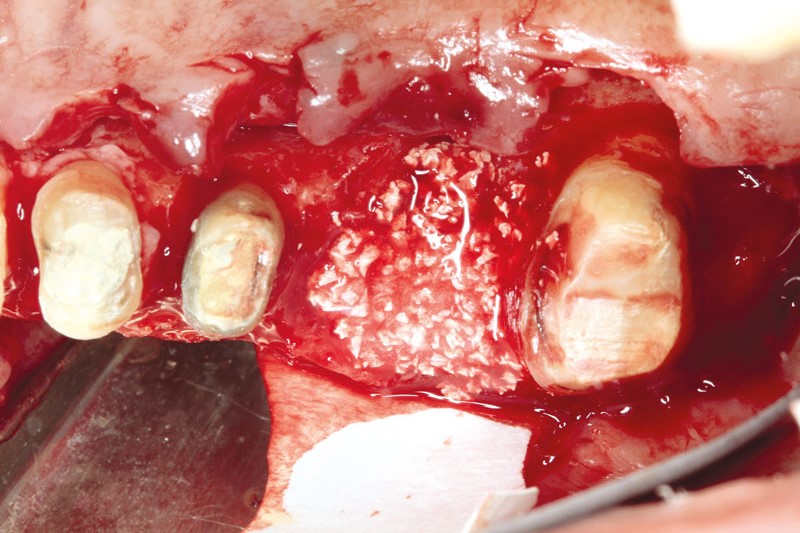

03/11 - cerabone® pre-mixed with Straumann® Emdogain® applied to the defect. Jason® membrane in place intended to cover the augmented area.

Ridge augmentation using cerabone®, Jason® membrane and Straumann® Emdogain® - Dr. S. Pelekanos